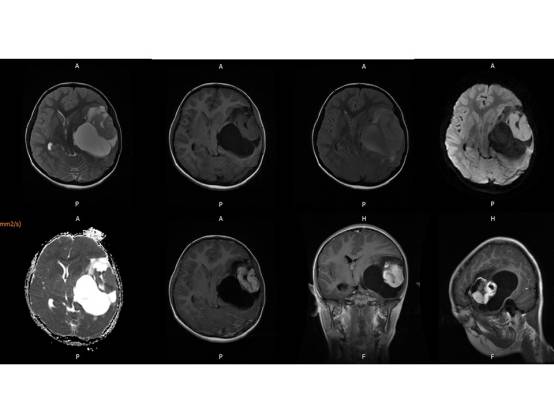

MR平扫及增强示:

左侧颞叶见大块状等长T1等长T2异常信号,FLAIR呈高新,DWI(b=1000)实质部分呈稍高信号,ADC实质部分呈等信号,边界尚清,周围脑实质受压。注入GD-DTPA后病变实质部分呈明显强化。

(左颞)血管周细胞瘤WHO II级。

结果7例肿瘤均位于颅内脑外,单发,体积较大,边界清楚,可见分叶,T1WI示肿瘤呈等信号或稍高信号,T2WI呈等信号或稍高信号,FLAIR呈稍高信号,DWI呈不均匀低信号,CT呈稍高密度影,增强扫描肿瘤实体性部分显著强化,内可见斑点、片状囊变或坏死区;4例可见脑膜尾征,肿瘤内及周边见血管流空或强化血管倍号; 瘤周水肿随肿瘤增大而明显;结论颅内血管周细胞瘤(HPC)是一种少见颅内脑外肿痫,肿痫形态不规则,边缘有分叶,增强扫描显著强化,内均可见斑点、片状囊变、坏死无强化区,瘤内无钙化,肿瘤周边可见血管流空信号,肿瘤恶变时,可见大片坏死出血,肿痛可侵犯破坏周围脑组织和骨组织,但无骨质增生。